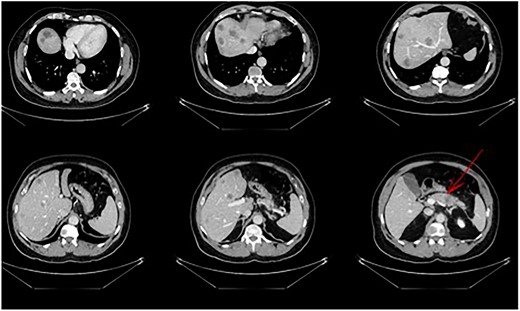

A 56-year-old male in good clinical condition presented at our outpatient clinic with pancreatic-body carcinoma and >25 synchronic LMs. A triple-phase computer tomography (CT) scan of the liver with intravenous contrast confirmed a 2.3-cm ill-defined hypodense lesion in the body of the pancreas and numerous ill-defined lesions, ranging from 1- to 3-cm in size, located in both liver lobes. Small peripancreatic lymph nodes were also noted (Fig. 1). A bone scan and whole-body CT scan were otherwise unremarkable. Serum levels of the tumor markers CA19-9 and CEA were 4730 U/ml and 138 ng/ml, respectively.

Pancreatic tail/body cancer (red arrow) with multiple liver lesions.